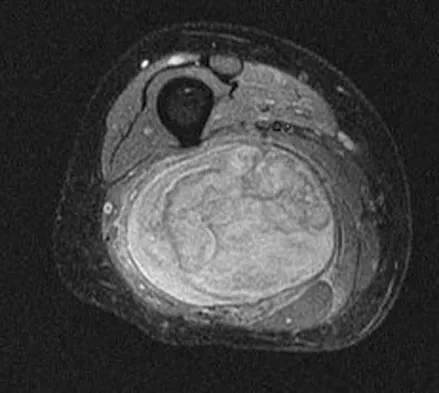

A 28-year-old man reports knee stiffness, swelling, and a constant ache that is worse with activity. Examination reveals an effusion, global tenderness, and warmth to the touch. Flexion is limited to 110 degrees. Figures 48a through 48d show sagittal T1-weighted, sagittal T2-weighted, axial T1-weighted fat-saturated gadolinium, and axial gradient echo MRI scans. Based on these findings, what is the most likely diagnosis?

Explanation